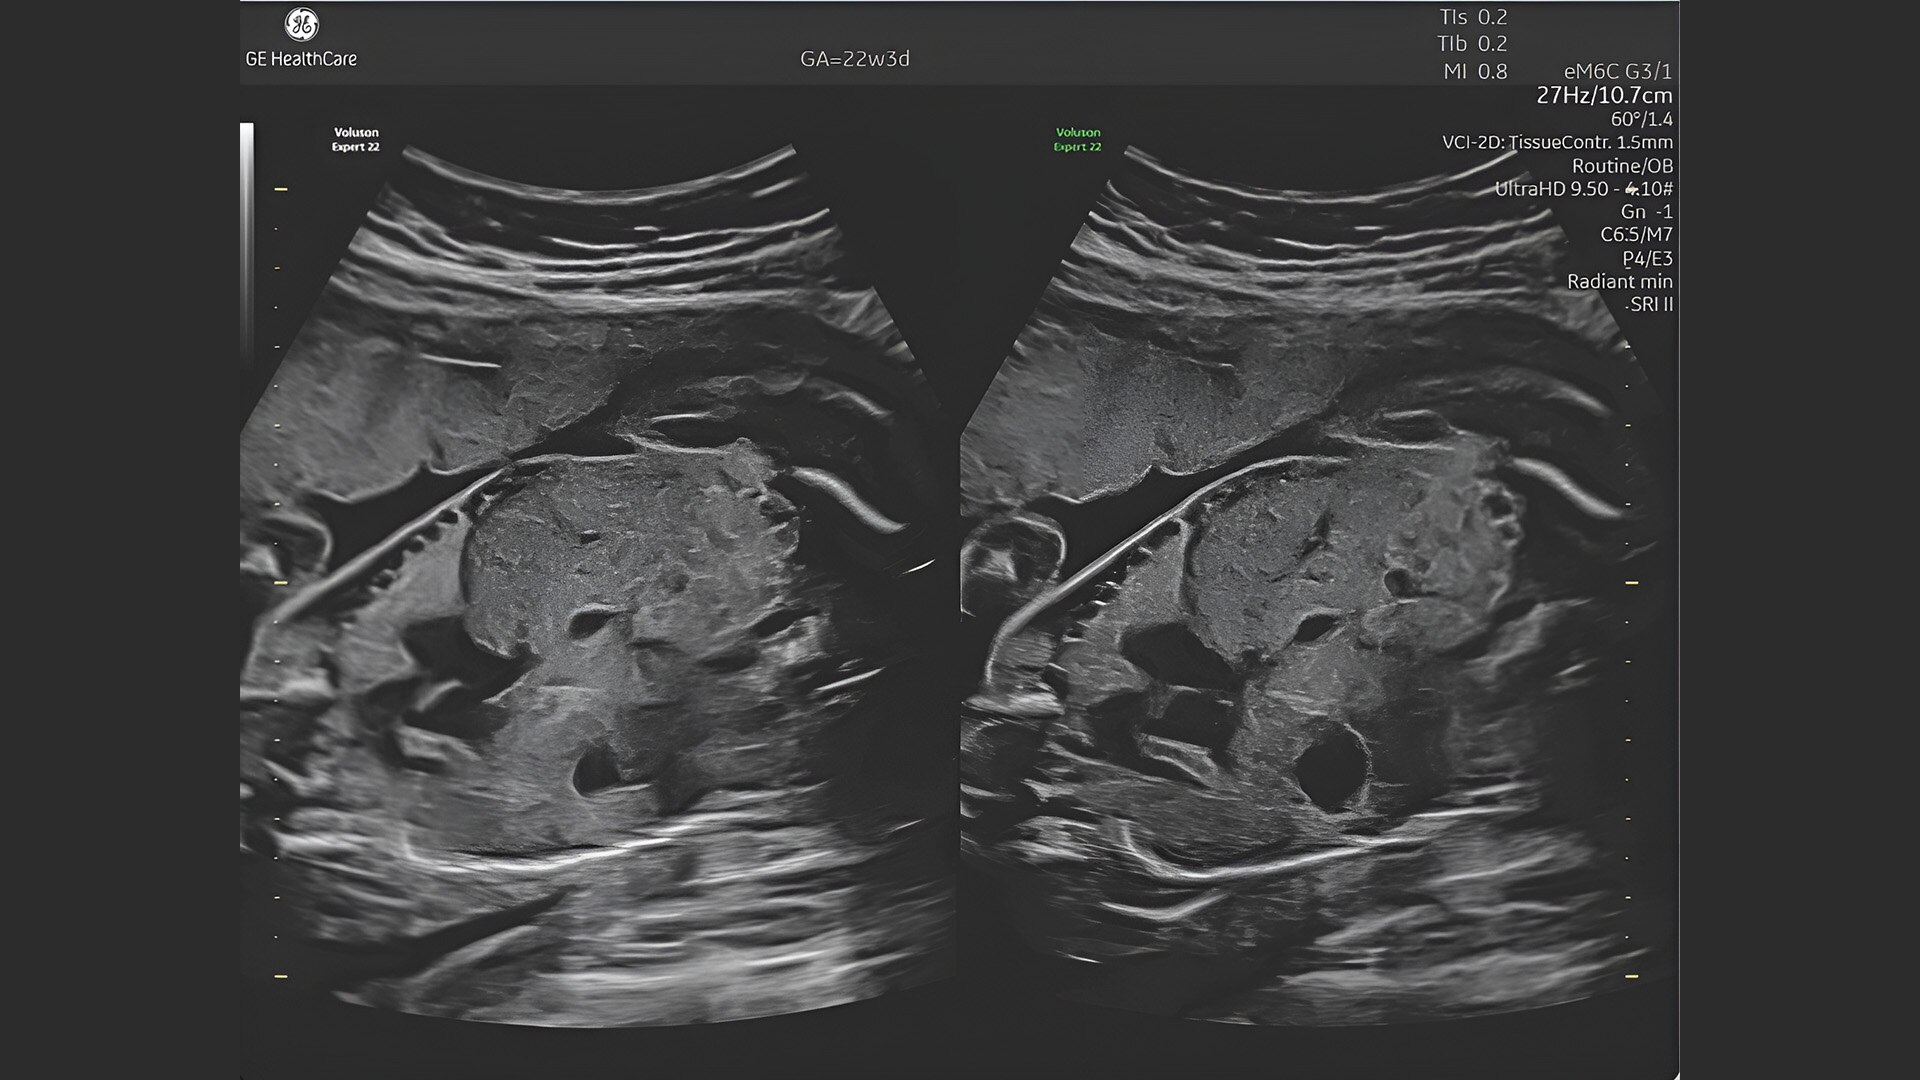

Complex cases come with enough uncertainty. That's why the Voluson Expert 22 is specifically designed for in-depth assessment of complicated anatomy — with pioneering first trimester, fetal cardiac, gynecological, and other pivotal technologies that focus on early detection and intervention.

Identifying fetal cardiac abnormalities earlier means you can intervene sooner, plan for delivery, and potentially improve outcomes. The Voluson Expert 22 provides a full solution of progressive tools, to help distinguish the tiniest structures with stunning clarity to provide patient answers faster.